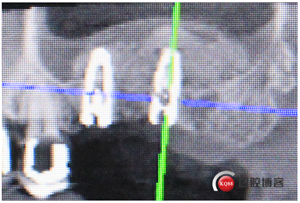

再看看片子。

問(wèn)題在這里,不給留位置怎么會(huì)有齦乳頭,沒(méi)有間隙怎么清潔?這完全是技工的錯(cuò)吧?算了我自己修整一下吧。